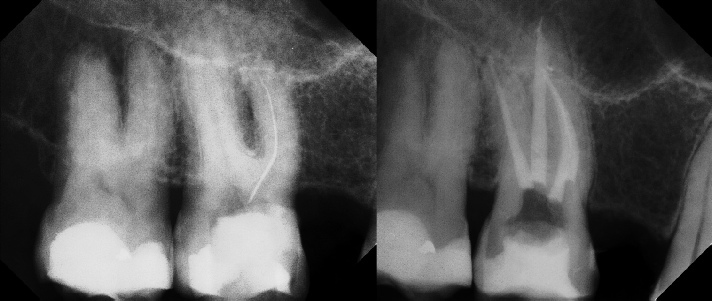

Pre-op Post-op 1 Post-op 2